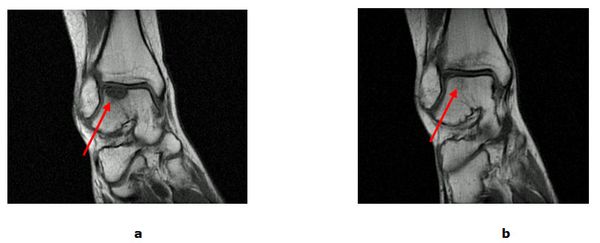

Bei isolierten Knorpel/Knochen Verletzungen (Osteochondrale Läsion, Osteochondrosis dissecans) kann während einer Gelenkspiegelung eine vitalisierende Anbohrung des Knochens erfolgen. Besteht bereits ein ausgeprägter Knorpelschaden wird mit einem speziellen Instrumentarium die harte Knochenschicht durchbrochen und die Bildung von Ersatzknorpel angeregt (Mikrofrakturierung). Der freie Gelenkkörper wird vorher entfernt. Dauerhaft schmerzhafte umschriebene Knorpelläsionen können durch die Verpflanzung eines Knorpel-Knochen-Zylinder (Mosaikplastik, Knorpel-Knochen-Zylinder Transplantation) therapiert werden. Aus einem gesunden nicht belasteten Gelenkanteil wird ein Knorpel-Knochen Zylinder entnommen und in der sog. „Press fit“ Technik am Sprungbein eingesetzt. Ein anderes Verfahren, die sog. MACT eignet sich zur Therapie großer Defektzonen. Bei der MACT (Matrix gekoppelte Autologe Chondrozyten Transplantation) wird Knorpel entnommen und an ein Speziallabor geschickt. Die entscheidenden Zellen werden isoliert, vermehrt und in einer Zweitoperation auf den Knorpeldefekt aufgebracht.

Abb.4: a MRT (Kernspintomografie) vor der Mikrofrakturierung mit Knorpel-Knochen Schaden (Pfeil). b 8 Monate nach erfolgter Therapie mit revitalisiertem Gewebe (Pfeil).